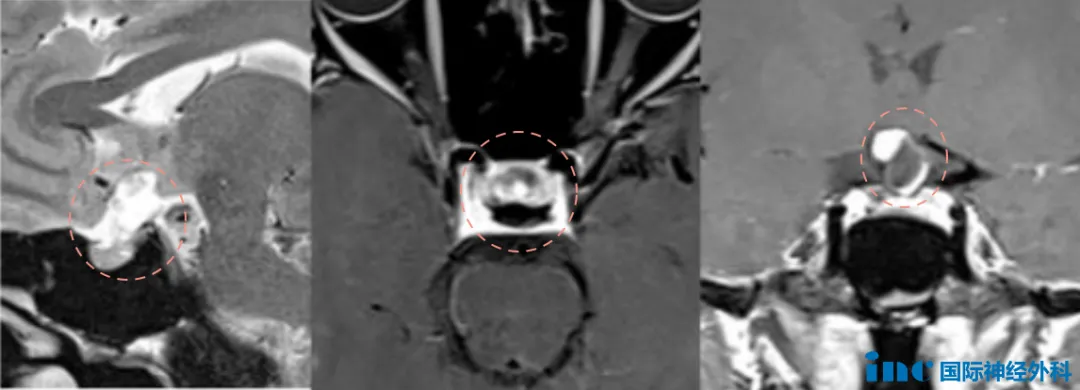

这是赵女士术前MRI,可能看到这个影像你还没有什么感觉,那我们先看看大脑鞍区的情况:从眉心再往里大概四五厘米的位置,它是颅中窝中央部的蝶鞍及其周围区域。地方虽然不大,只有大约5.5平方厘米,却是众多关乎生命结构的汇集地——如颈动脉、基底动脉、海绵窦、垂体、下丘脑、视神经等多组颅神经等......视神经跟视力有关系,垂体柄跟内分泌有关系,下丘脑决定病人认知能力和术后内分泌功能。颈内动脉这些大血管就不言而喻了,损伤可能都是致命性的。

在绝望与希望的交织中,赵女士一家没有放弃,他们像一叶扁舟,在茫茫大海中奋力寻找着生命的灯塔。2024年8月,头颅MRI的检查结果如同一道闪电——鞍上区的颅咽管瘤,这个隐藏在光明背后的恶魔,终于露出了它的真面目。原来,这一切的根源,竟是一个小小的肿瘤,它悄然生长,却带来了如此巨大的影响。